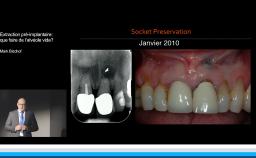

Edentement au secteur anterieur: le défi pour une esthetique optimale

A partir de la description des facteurs de risque esthétique du bloc incisivo-canin maxillaire, de la présence d’os et de gencive autour des implants, le conférencier présente une succession de cas cliniques décrivant ses procédures chirurgicales et prothétiques.

• Ridge Preservation